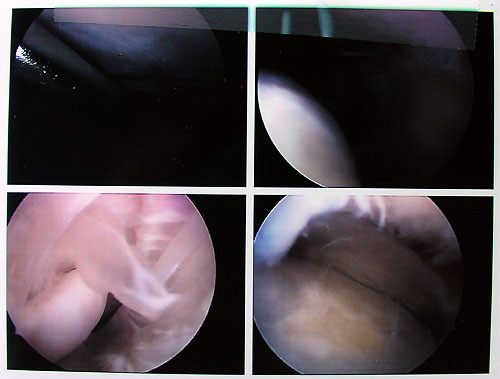

Freitag, 26. August: Alle Fäden draussen

Klicken für grössere FassungHeute wurden alle Fäden gezogen, die dritte Physio lief gut - langsam habe ichs gut im Griff, wieviel ich forcieren darf, ohne nachher allzu starke Schmerzen Klicken für grössere Fassungzu haben. Allzu lange halte ichs nicht aus, ohne das Bein hochzulagern; der Bluterguss ist aber schön zurückgegangen und das ganze sieht recht gut aus. Der Befehl lautet: Hochlagern, so viel üben wie schmerzfrei geht, das Gelenk in Bewegung halten. - Fast vergessen: In meiner Akte habe ich ein neues Arthroskopiebild entdeckt.

9. August 2005, 10.15 Uhr: Ansichten eines Knies

Knie von innen - klicken für grössere FassungNun sieht man dieses vermaledeite Gelenk endlich mal von innen! Ich erkenne zwar nichts - aber falls jemand mehr aus diesen Strukturen rauslesen kann, bin ich dankbar für Informationen... Bitte auf das Foto klicken für eine grössere Fassung! (Auf dem Bild rechts oben, wie mir inzwischen erklärt wurde, ist unten das Tibiaplateau sichtbar, oben die Gelenkfläche des Oberschenkels, hinten der Meniskus - die unregelmässige Fläche bedeutet, dass ich eine für mein Alter massiv fortgeschrittene Arthrose habe. Im Bild links unten ist ein Teil eines nachträglich entfernten Knochenfragmentes im Hintergrund sichtbar.)